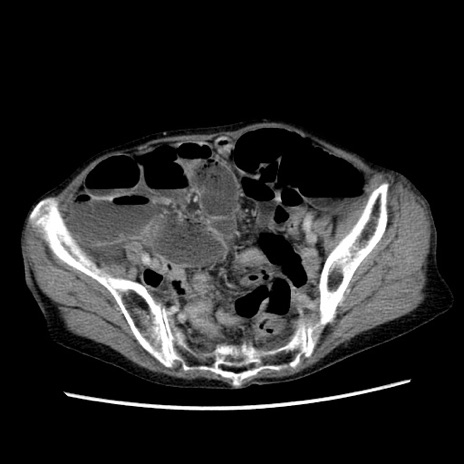

冠状断像

症例25(横断像)

【症例】80歳代女性

【主訴】胸のつかえ感

【現病歴】約9時間前に食後から胸のつかえた感じあり、嘔吐あり、来院。

【既往歴】胃癌(全摘)、胆摘、虫垂炎

【身体所見】心窩部に圧痛あり、反跳痛なし。

【データ】WBC 5700、CRP 0.05